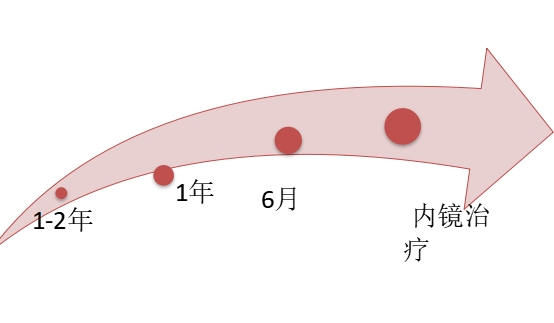

6.3. 定期复查胃镜

一般建议复查胃镜的频率: